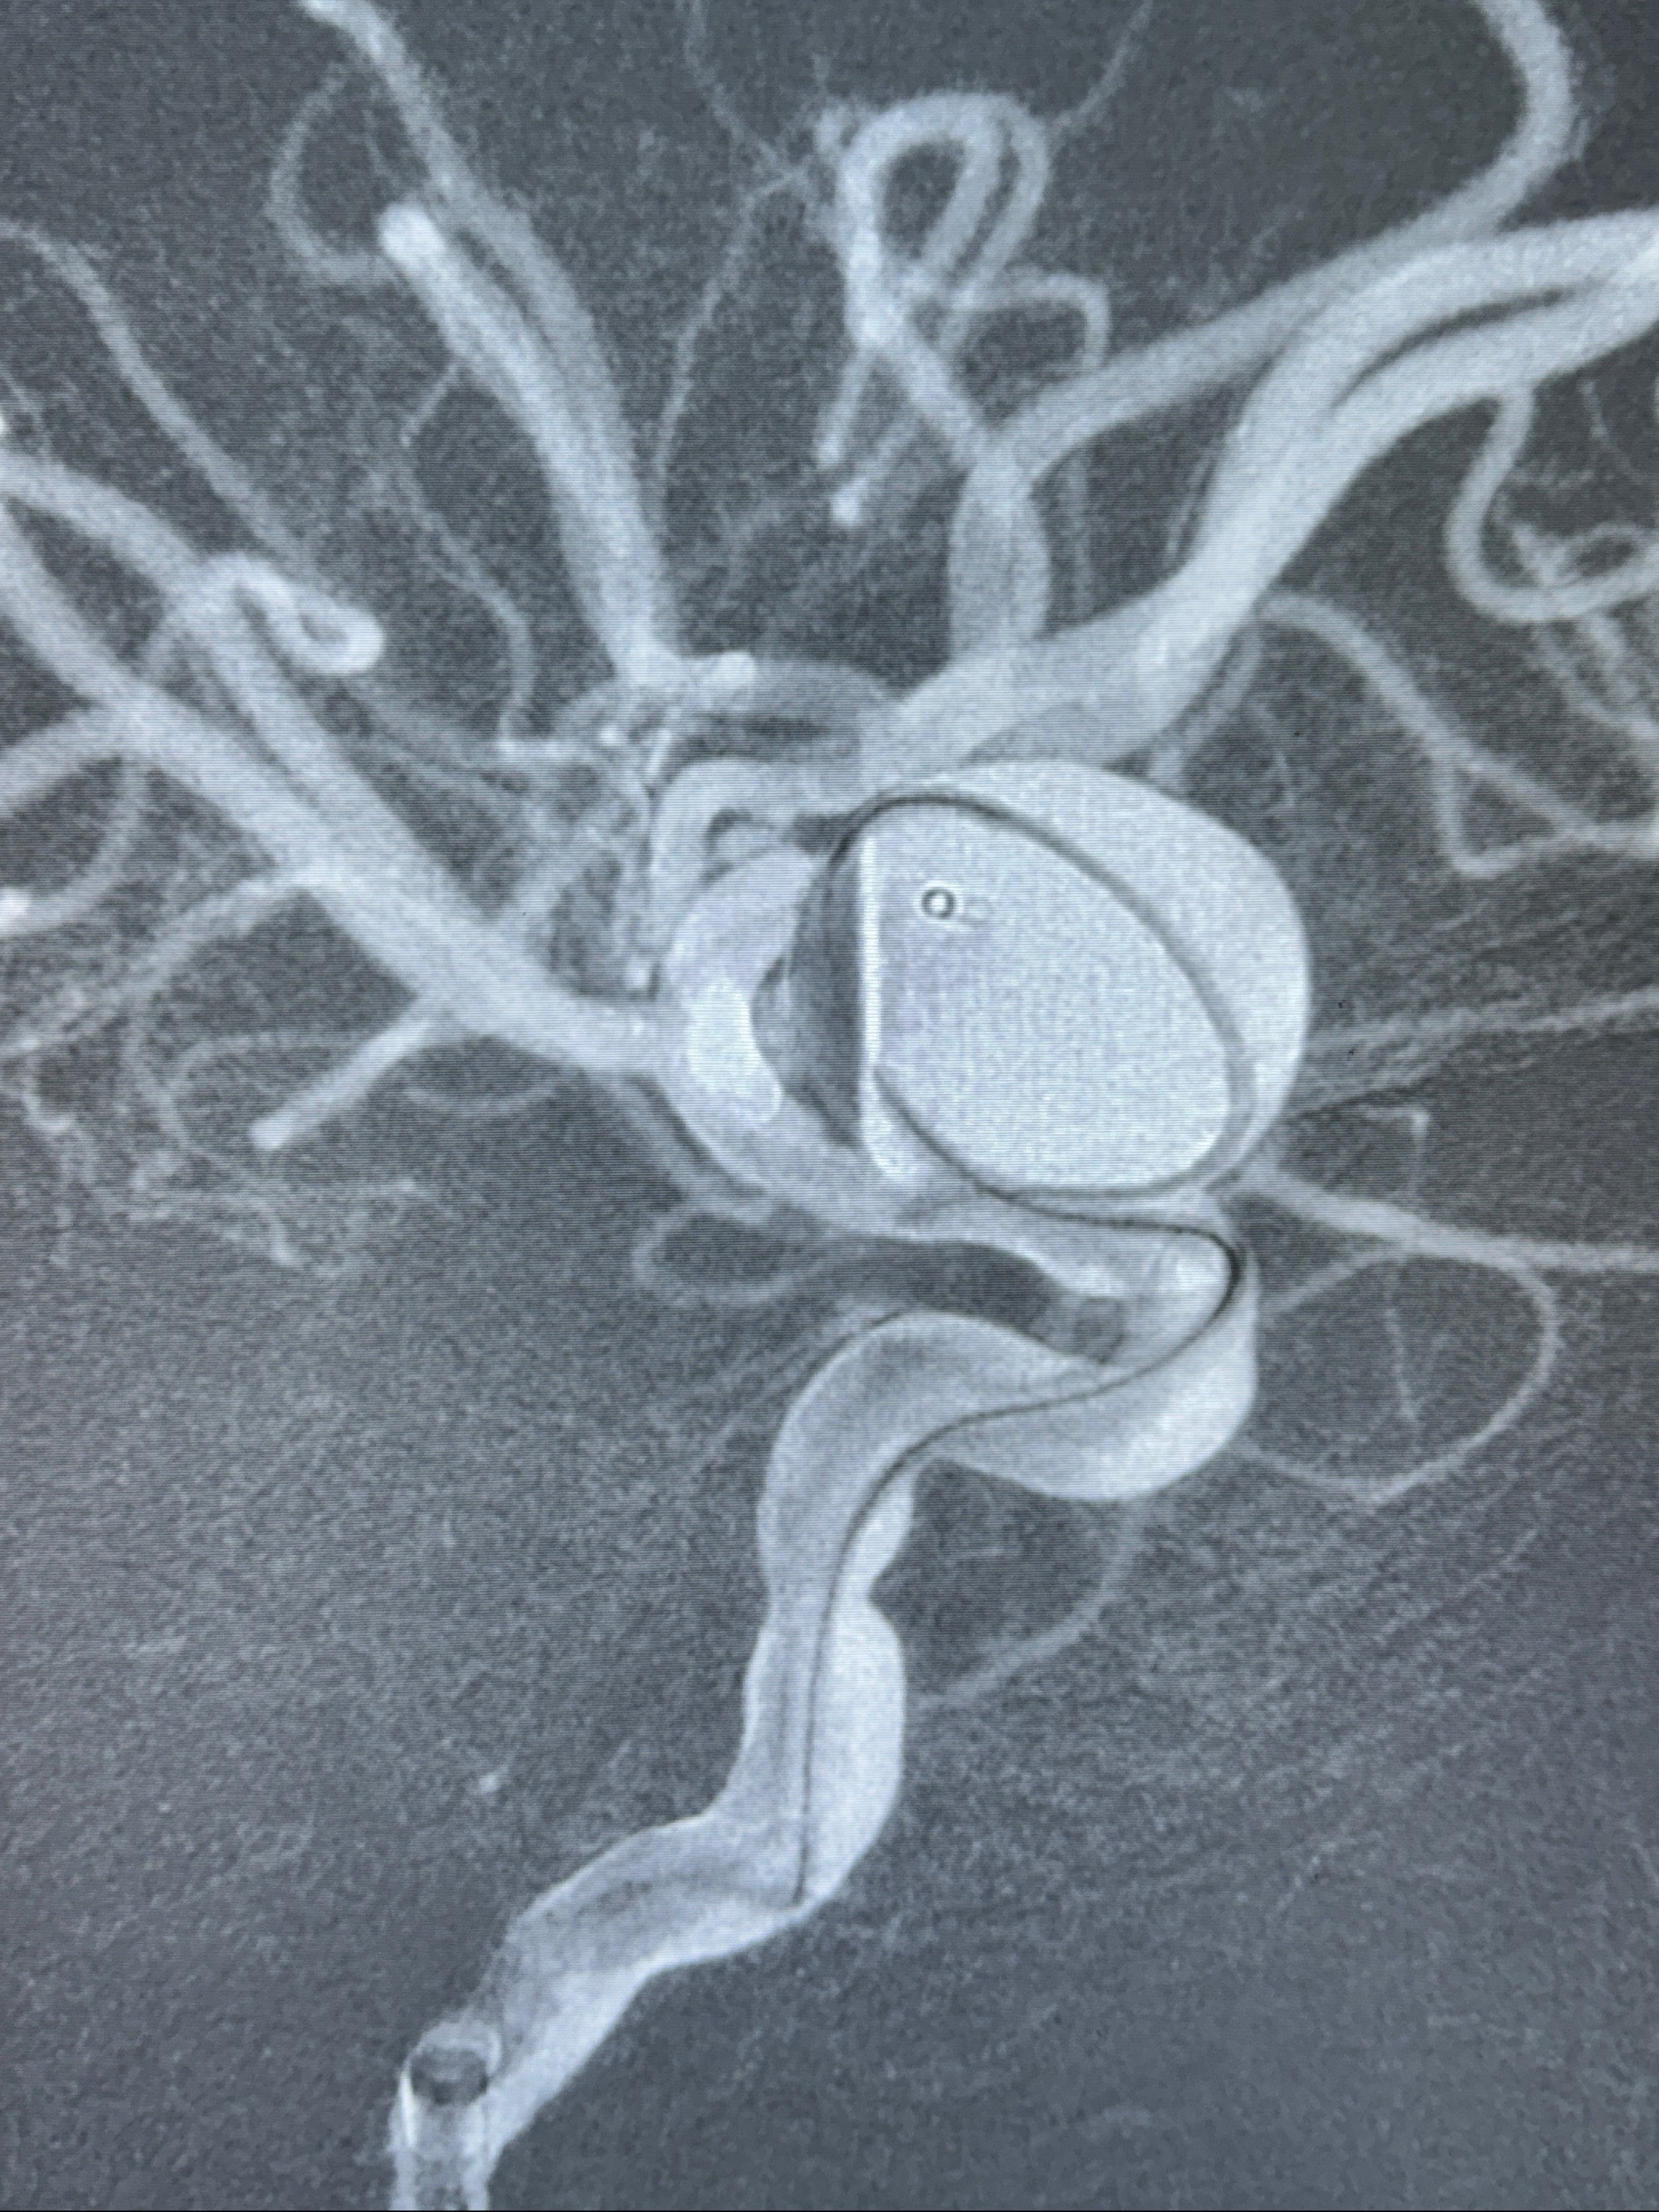

2023-12-27术后第十天复查DSA

支架贴壁佳,但可见射流,咋办?

2024-01-08全麻下再行植入密网支架一枚

Tubridge 4.5-35mm

支架植入顺利,贴壁佳,支架内血流通畅,动脉瘤内血液滞留明显